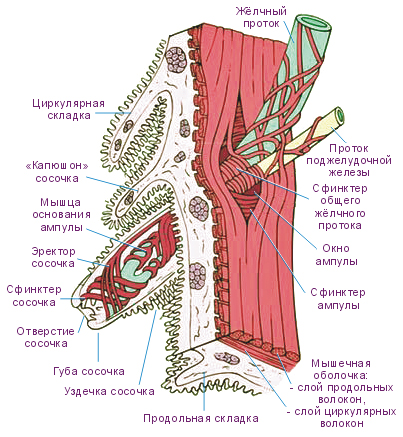

Анатомия и особенности Гартманова кармана желчного пузыря